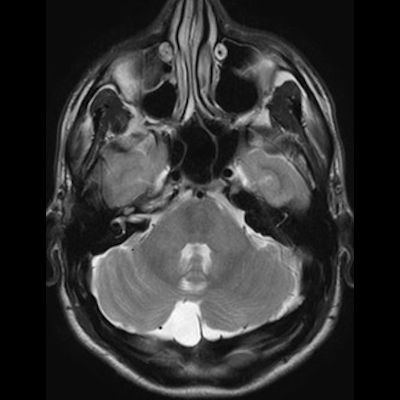

11 ay, Nöbet

Charlevoix-Saguenay Otozomal Resesif Spastik Ataksisi (ARSACS)

ARSACS (Charlevoix-Saguenay otozomal resesif spastik ataksisi) Sendromu

ARSACS

Autosomal recessive spastic ataxia of Charlevoix-Saguenay

Serebellar folya sinapsisi